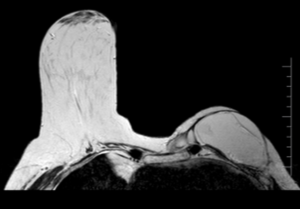

52 year old lady with right breast mass of recent onset.

What is the mass?

Clue: She is IDDM since 15 years